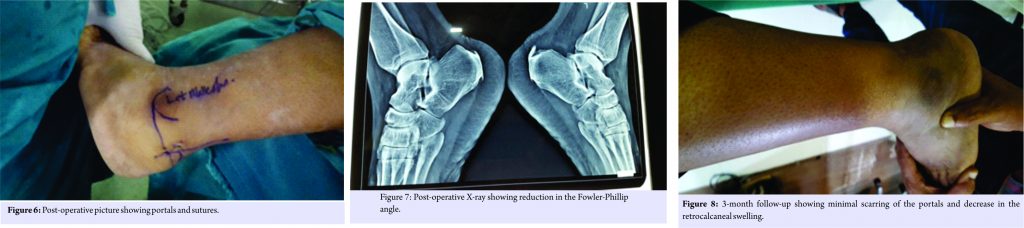

Then, an accessory lateral portal is created by giving a stab incision below the posterolateral portal using a needle as a guide so as to reach the posterolateral corner of the calcaneum. A stab incision is given, spread with mosquito forceps while entering the retrocalcaneal space. The bursa is shaved with a shaver tip facing away from the Achilles tendon. The medial and lateral corners of the Haglund’s bump are viewed after the bursa is shaved off. An osteotome is passed through the accessory lateral portal (Fig. 3) and the Haglund’s bump is removed and is confirmed on fluoroscopy and by plantar flexing the ankle to see whether the sufficient amount has been removed or not. The sharp edges are smoothened using an acromioniser (Fig. 4 and 5). The skin is closed using non-absorbable sutures, and pressure dressing is applied, tourniquet is released (Fig. 6).

The patient started full ankle range of movements and weight-bearing as tolerated from the 1st post-operative day (P.O.D). He was discharged on the 2nd P.O.D after primary dressing and suture removal was done on the 12th P.O.D. Patient started full weight-bearing from the 13th P.O.D. His post-operative X-ray showed reduction in Fowler-Phillip angle from 71 to 45 (Fig. 7). We did not encounter any complications during intraoperative and post-operative follow-up period. He was followed on the 1st, 3rd, and 6 months postoperation and his AOFAS score improved from 64 to 98 at 6-month follow up. Patient is pleased as there was no swelling in the retrocalcaneal region with minimal scar tissue formation (Fig. 8) and early rehabilitation.